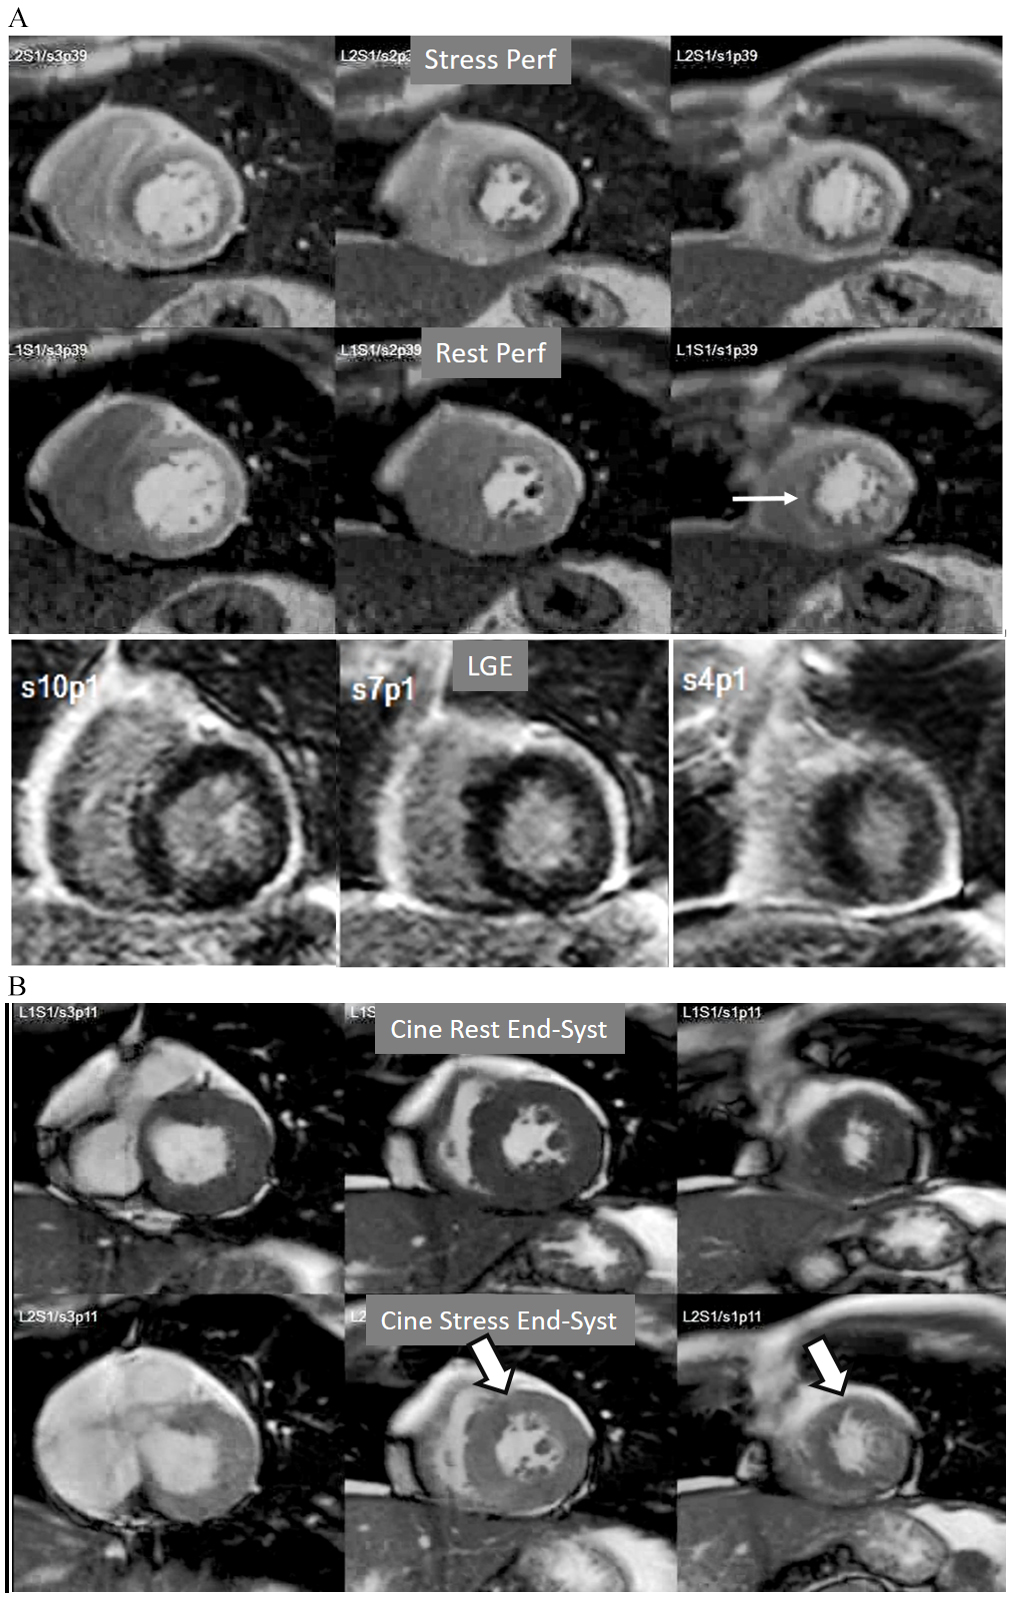

Fig. 13.Perfusion artifact. Artifactual stress perfusion defect (arrows) not present at rest, leading to angiography which did not show CAD (right panels).